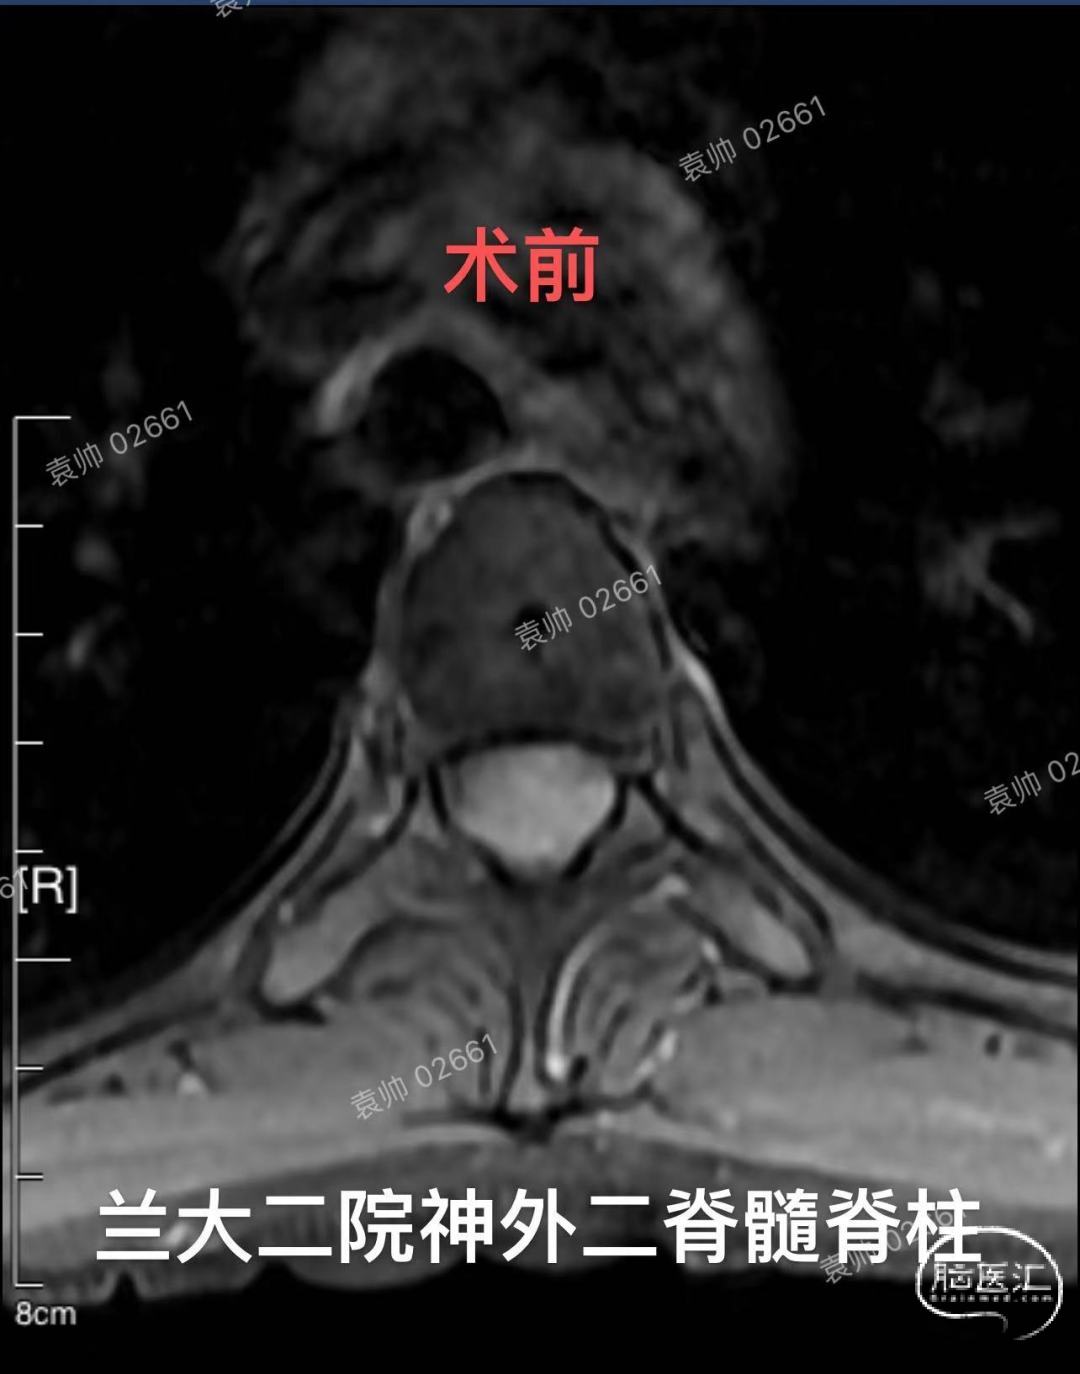

兰州大学第二医院神经外科二病区脊髓脊柱组病例分享:20岁年轻女性,T3-4脊髓背侧脊膜瘤。对于胸段脊膜瘤的治疗,大家都不陌生,手术难度不大,术后复发率低。但是相对于大多数凸面脑膜瘤,可以做到肿瘤基底硬膜全切,达到Simpson 1级切除,脊膜瘤全切附着硬脊膜,重建困难,容易术后脑脊液漏,并且对于年轻患者,不能完全避免肿瘤复发。由于硬脊膜内外层易于剥离,不同于硬脑膜,而脊膜瘤通常只会侵及内层硬膜,所以,我们推荐使用Saito技术,以剥除肿瘤附着硬脊膜内层,达到近似Simpson 1级切除的效果,可以有效预防肿瘤复发。